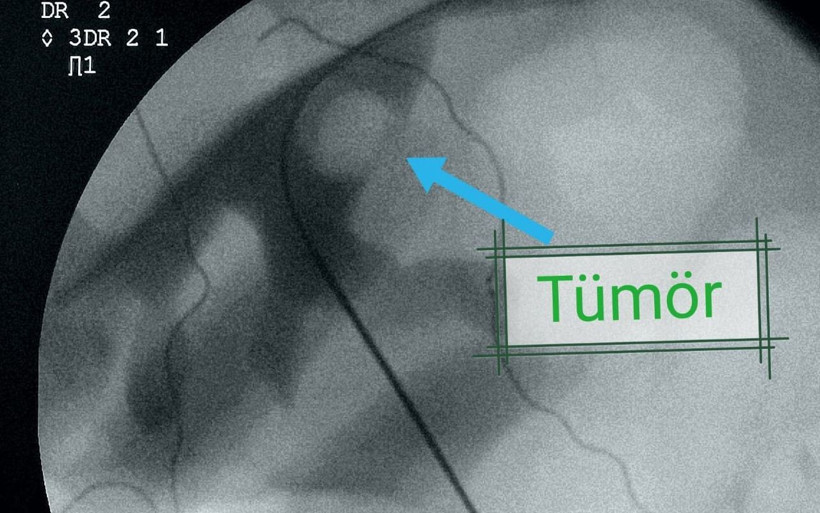

ELAZIĞ'da 54 yaşındaki Fuat Salar, yaşamını devam ettirdiği tek böbreğinde görülen tümör sonrası uygulanan "Perkütan" yöntemiyle dünyada 84'üncü vaka olarak kayda geçti.

Böbreğinin içine kadar girildi: Burada Üroloji Uzmanı Op. Dr. Serhat Yentür’ün tedavisine başladığı Salar, yapılan tetkikler sonucunda böbreğinde 3 santimetrelik lezyon ve tümöral hücreler saptandı. Bunun üzerine zor ve riskli olan ‘Perkütan’ yöntemi ile operasyon planlandı. Operasyonda Salar’ın böbreğine yandan girilip orada bir tüp oluşturulduktan sonra böbreğin içine girildi.

Ardından hastadaki tümör tur aletleriyle kazındı. Başarılı geçen ameliyatın ardından Salar, 3 gün sonra taburcu edilirken, perkütan yöntemi ile dünya literatüründe 84’üncü vaka olarak kayıtlara geçtiği öğrenildi.